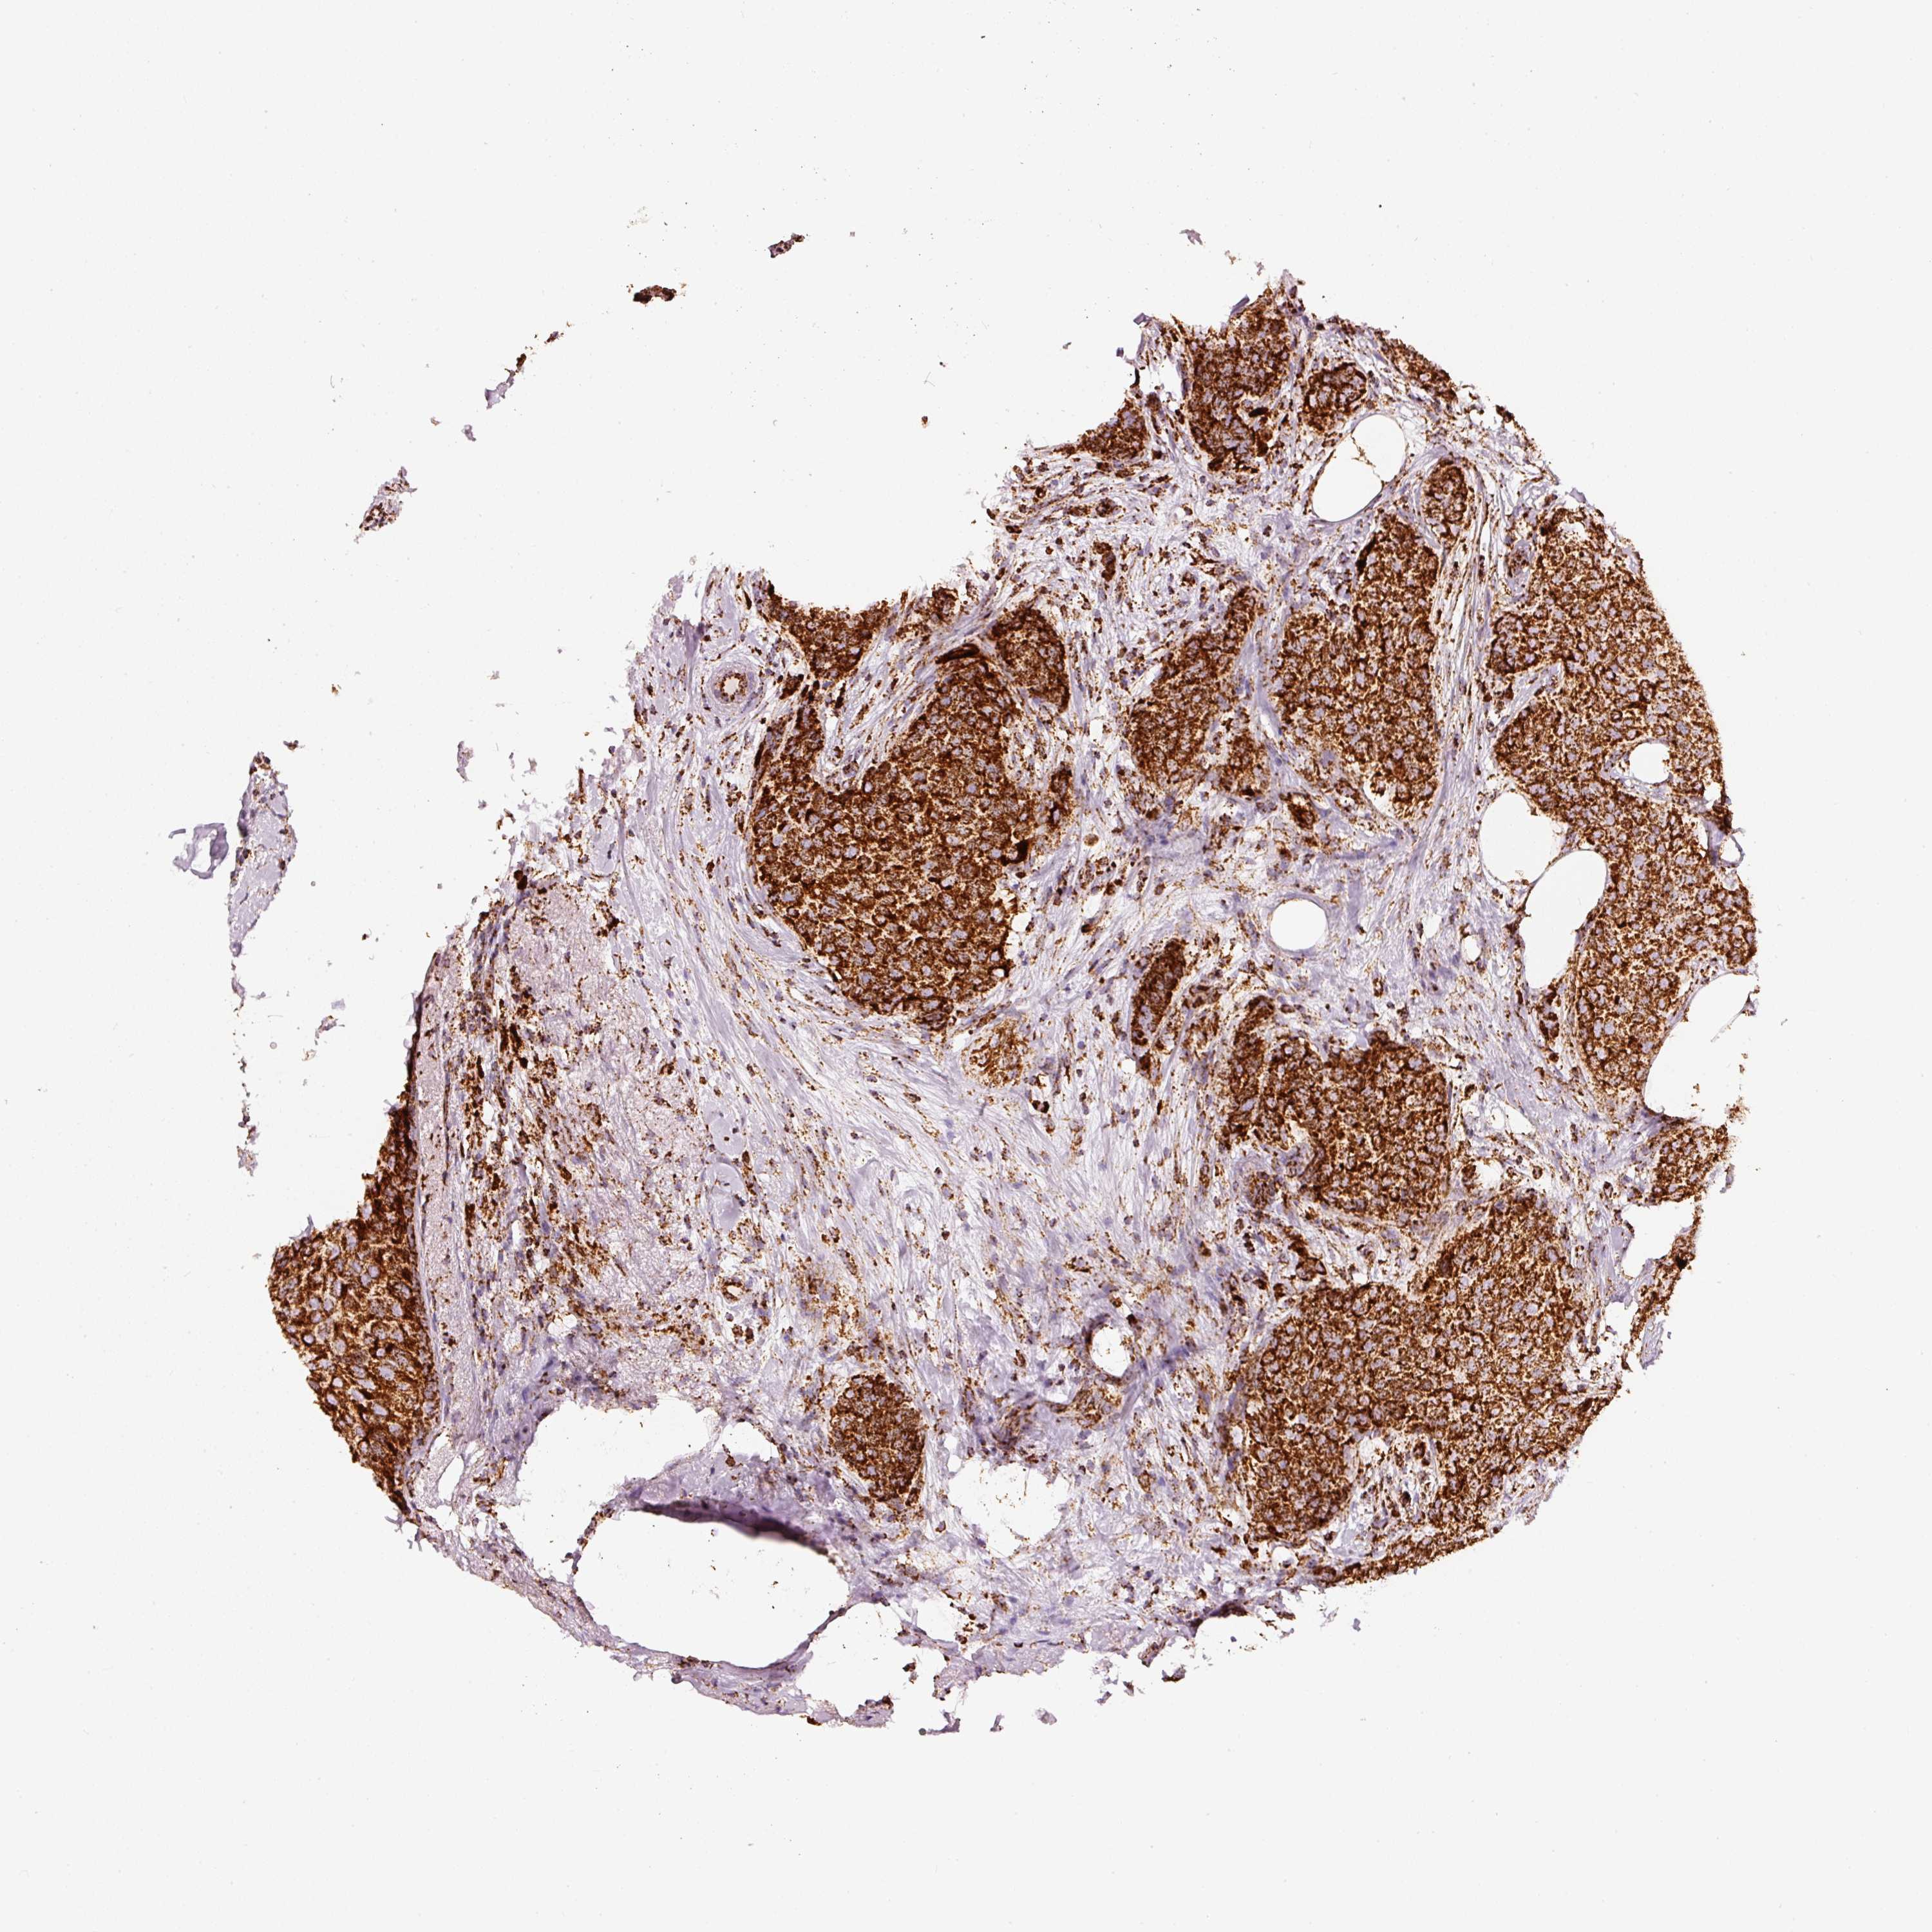

BRCA TCGA BRCA VALIDATION PROTEIN EXPRESSION

ANTIBODIES

AND

VALIDATION